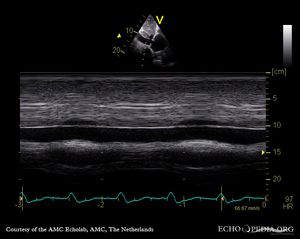

신체 검사는 폐고혈압의 전형적인 징후를 찾기 위해 수행되며, 이 질환이 유전될 수 있는지 여부를 결정하기 위해 자세한 가족력 조사가 이루어진다.[55][56][57][58] 벤플루렉스(펜플루라민 유도체), 다사티닙, 코카인, 메스암페타민, 에탄올로 인한 간경변, 담배로 인한 폐기종과 같은 약물 노출 병력도 중요하다.[13][59][22] 임신 중(특히 임신 후기) 선택적 세로토닌 재흡수 억제제 사용은 아기가 신생아 지속성 폐고혈압을 겪을 위험 증가와 관련이 있다.[22]6. 2. 심장 초음파 검사

폐고혈압이 의심되는 경우, 심장 초음파 검사를 시행한다.[12][13][58] 도플러 심장 초음파의 메타 분석은 우심도자술 결과를 예측하는데 각각 88%와 56%의 민감도 및 특이도를 보고했다.[60] 따라서 도플러 심장 초음파 검사로 폐고혈압의 존재를 시사할 수 있지만, 우폐동 카테터 삽입술이 PAH 진단의 금본위적 표준으로 남아있다.[12][13]

심장 초음파 검사는 선천성 심장병을 감지하여 폐고혈압의 원인을 파악하는 데에도 도움이 될 수 있다.[12]